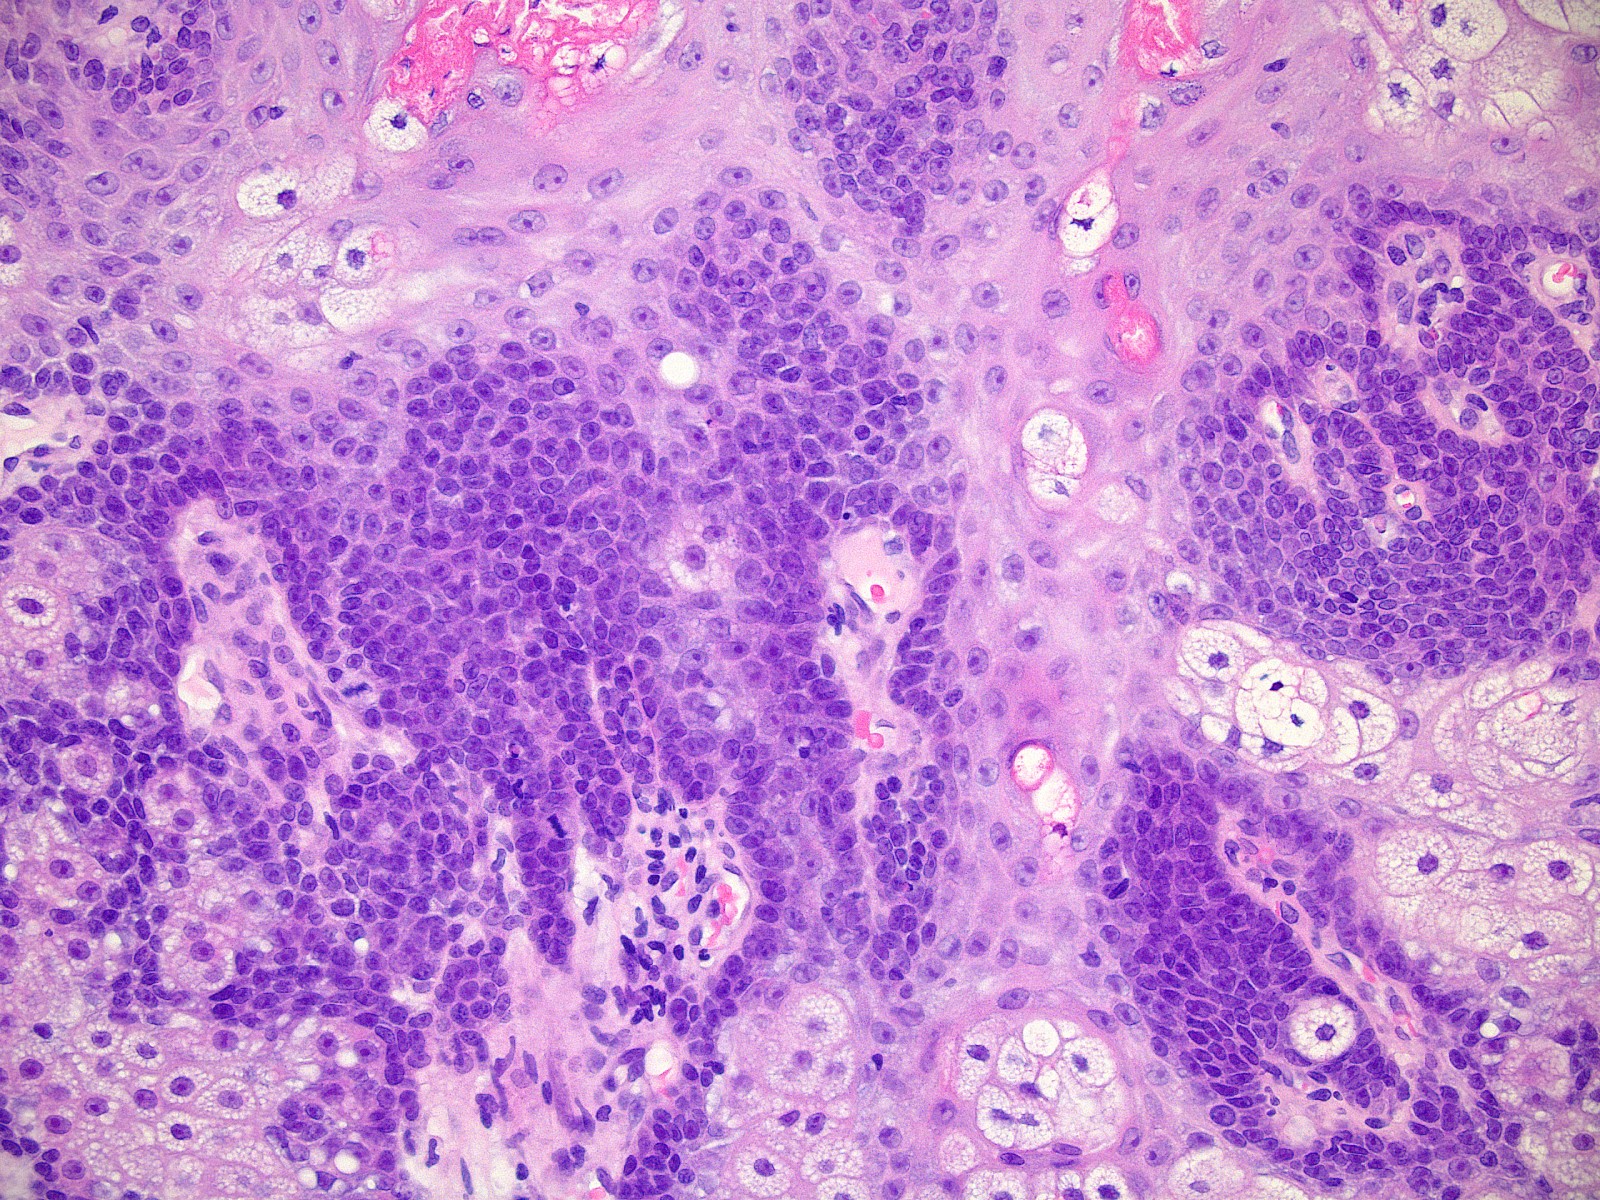

Microscopic (histologic) images

- Well circumscribed, nodular growth of lobules consist of admixture of basaloid cells and mature sebocytes

- Basaloid cells are usually located at the periphery of lobules and sebaceous cells with intracytoplasmic lipid vacuoles, which are usually located at the center of lobules

- Basaloid cells are composed of expanded germinative layer, with more than the normal 2 cell layers seen in mature sebaceous glands or sebaceous hyperplasia but still less than 50% of the tumor volume (> 50% is seen in sebaceoma / sebaceous epithelioma)

- Increased mitotic activity is sometimes seen in the basaloid cell component (Surg Pathol Clin 2017;10:367)